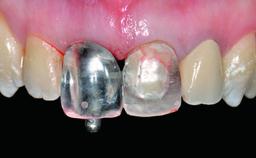

Replacement of a Perforated Upper Left Central Incisor: Early Placement of an RC Bone Level Implant

A 28-year-old patient presented at her general dentist’s office and complained about the appearance of her tooth 21. The patient had a history of trauma to this tooth. Endodontic treatment had been performed in the past and a crown placed on the tooth. A procedure to replace the old crown was performed by her dentist; however, a perforation on the middle third of the root occurred, and extraction of tooth 21 was suggested. Upon clinical and radiographic examination of the patient, who had been referred to us, replacement of tooth 21 by a dental implant appeared to be indicated.

Abutment Type Customized